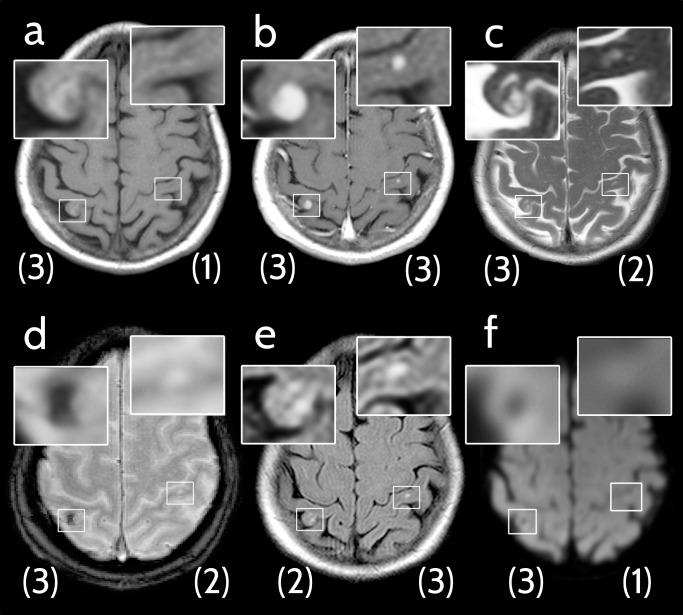

Medical records of all melanoma patients referred to our center between November 2005 and December 2016 were reviewed for presence of MBM. Analysis encompassed six MRI sequences at the time of initial diagnosis of first or new MBM, including non-enhanced T1-weighted (T1w), contrast-enhanced T1w (ceT1w), T2-weighted (T2w), T2w-FLAIR, susceptibility-weighted (SWI) and diffusion-weighted (DWI) MRI. Each lesion was rated with respect to its conspicuity (score from 0-not detectable to 3-clearly visible).

RESULTS

Of 1210 patients, 217 with MBM were included in the analysis and up to 5 lesions per patient were evaluated. A total of 720 metastases were assessed and all six sequences were available for 425 MBM. Sensitivity (conspicuity ≥2) was 99.7% for ceT1w, 77.0% for FLAIR, 64.7% for SWI, 61.0% for T2w, 56.7% for T1w, and 48.4% for DWI. Thirty-one (7.3%) of 425 lesions were only detectable by ceT1w but no other sequence.

CONCLUSIONS

Contrast-enhanced T1-weighting is more sensitive than all other sequences for detection of MBM. Disruption of the blood-brain-barrier is consistently an earlier sign in MBM than perifocal edema, signal loss on SWI or diffusion restriction.